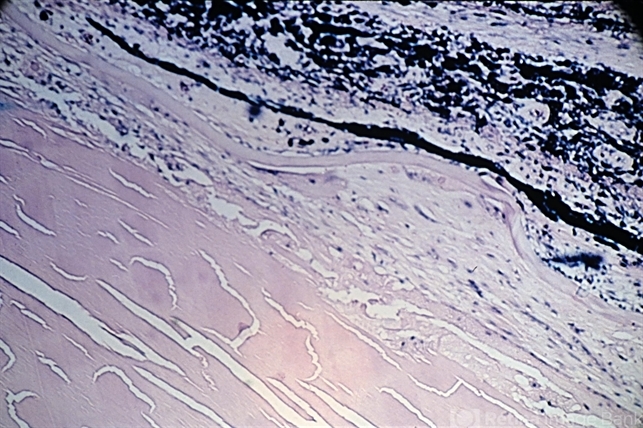

- anterior subcapsular polar cataract, pupillary membranes

- Anterior subcapsular cataract associated with severe inflammation of the anterior segment and an inflammatory pupillary membrane ( x40). (Scheie Eye Institute, No. 3952.)